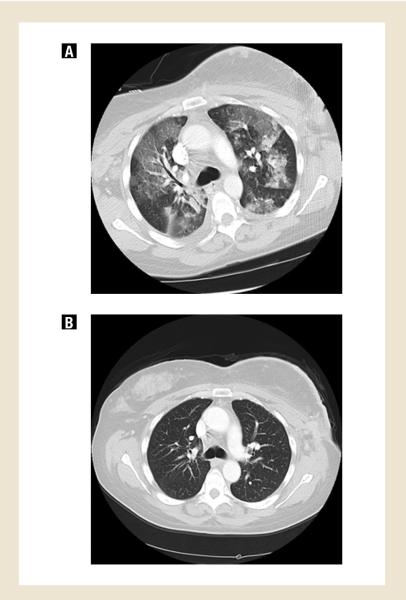

Three patients experienced possibly treatment-related serious adverse events. One patient experienced grade 4 hypoxia leading to discontinuation of protocol treatment. She presented with fever and cough 11 days after initiating saracatinib. Study drug was held, and broad-spectrum, empiric antibiotics were initiated. She quickly became hypoxic requiring intubation and vasopressor support. High-resolution CT scan of the chest demonstrated bilateral interstitial ground glass opacities and an ARDS-like picture; no pulmonary emboli were seen (Fig. 1a). A comprehensive infectious workup included negative bacterial, fungal, and viral cultures of blood and sputum. Legionella urinary antigens were negative. Bronchoscopy was negative for PCP and AFB, and cultures were negative; cytology was negative for malignant cells. An echocardiogram confirmed a normal left ventricular ejection fraction. Gr 2 adrenal insufficiency and hypotension were managed with hydrocortisone. With maximal supportive care and discontinuation of saracatinib, the patient gradually improved. Chest CT performed 18 days later showed resolution of the pulmonary infiltrates and confirmed stable disease (Fig. 1b). This patient was removed from study due to this possible drug-related pneumonitis.

Fig 1.

High resolution, chest CT scan of patient treated with saracatinib who experienced grade 4 hypoxia, possibly treatment-related. Figure 1A shows bilateral interstitial ground glass opacities 13 days after beginning study treatment. Figure 1B shows resolution of these findings 18 days after discontinuation of saracatinib, which corresponded to clinical improvement.